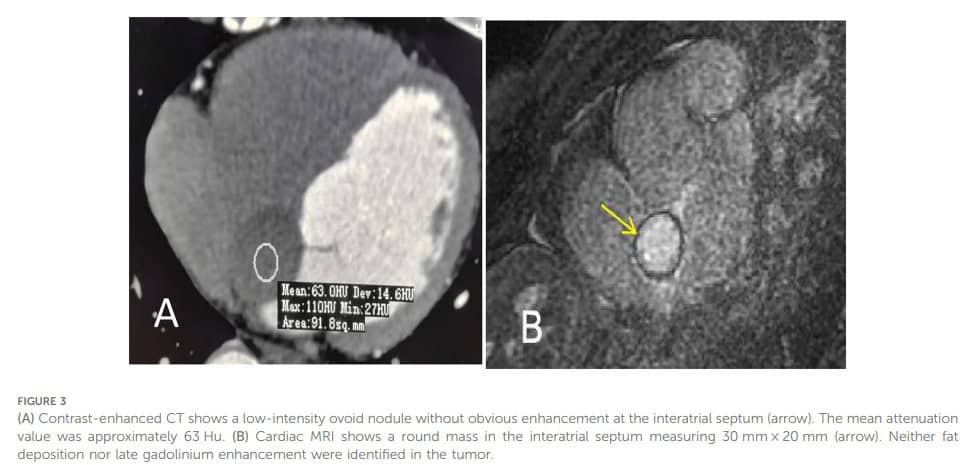

Realizado angiotomografia de artérias coronárias que descartou doença obstrutiva, confirmando a presença da lesão ovalada bem delimitada sem captação de contraste e sem vascularização.

A ressonância magnética cardíaca (B) descartou a possibilidade de deposição de tecido gorduroso e não mostrou realce tardio na lesão. Baseado em todos esses achados, a conclusão foi de se tratar de um cisto.